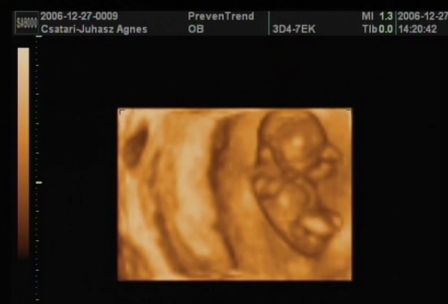

...Szerettem volna veletek megosztani, hogy hogy ficánkolt a drágám, de ilyen rossz hir után most képtelen vagyok!

A lényeg, hogy minden rendben van, és hogy uh szerint még nagyobb is egy héttel! Hallottam kalapálni a kis szivét, láttam a kezecskéit és a lábait...

A nyaki redőnk 0.7 vagyis tökéletes.

Január 23-án megyek a következő vérvételre az integrált teszt miatt!

Van dvd a kicsimről, csináltam nektek belőle képeket:

Kép Kép Kép Kép

Ági, köszönjük a képeket, nagyon jók lettek – szuper! Még a köldökzsinor is látszik :D és, még az is, ahogy a kezecskéit mozgatja.... jéééééé

Áááááááááági!!! Ez egyszerűen egy tökéletes bébike!!! És hogy már milyen nagy baba! Hihetetlen, hogy meg van mindene!!! Hol voltál 3D-s UH-n? Az integrált tesztet majd alkalomadtán meg fogom tőled kérdezni, mert most én is tervezek majd menni. Mindent meg akarok tenni a megnyugvásomért! Remélem, most már maximálisan nyugodt vagy a kis bébit illetően!

Amugy a Bolgárkerék utcában voltam integrált teszten. Ha jól tudom még Juci is ott volt. Isten igazából nem is a 3D-s volt a nagy része a vizsgálatnak, hanem, hogy a Down-kór szűrés. És az egészben az a jó, hogy pont az én dokibácsim van ott az uh-on! :) Mindent megmért, a combcsonttól kezdve a pulzust, az orrcsontot, a fejét... A 3D-sből ennyit csinált amit láttok. Majd késöbb elmegyek mégegyszer, amikor majd a szivét is jól látni, és akkor is csináltatok dvd-t.

Ez egyszerűen csodálatos volt! Úgy mozgolódott, sőt a látjátok a méhem milyen alakú... A drágám feljebb ugrált és onnan "csúszdázott le" (a doki ezt a szót használta). Csodálatos volt látni mindent. Sőt a doki még azt is megnézte, hogy mi van a lába között... Azt mondta csak tipp, és hogy ne vegyük készpénznek, de mintha lenne valami a lába között :D ...azért én még reménykedek,hogy kiscsaj, mert megnéztem a könyvben (csodálatos utazásban), hogy ilyenkor még a lányoknak is kitüremkedik, és nem lehet igazán megkülönböztetni! :roll: :lol:

És igen, kicsit megnyugodtam. Bár egy mondat megmaradt bennem és tudom, hogy azt fogom várni majd a következő uh-on: "gyomor és hólyag telítődése jelenleg nem ábrázolódik" De szerintem ehhez még kicsik is vagyunk... :(